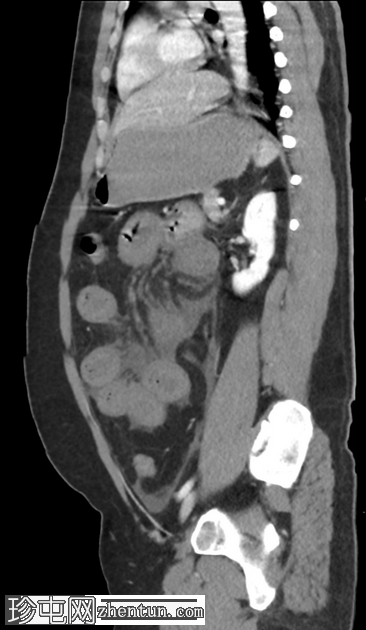

矢状C+门静脉期

肠系膜上静脉及其主要支流广泛血栓形成,延伸至脾静脉和门静脉,包括门静脉右支和近端左支。

小肠管增厚、水肿、低灌注,提示小肠缺血。

由于门静脉右支血栓形成,肝右叶低灌注,导致短暂性肝密度差(THAD)。

胃部膨胀,充满液体。

腹部少量游离液体。